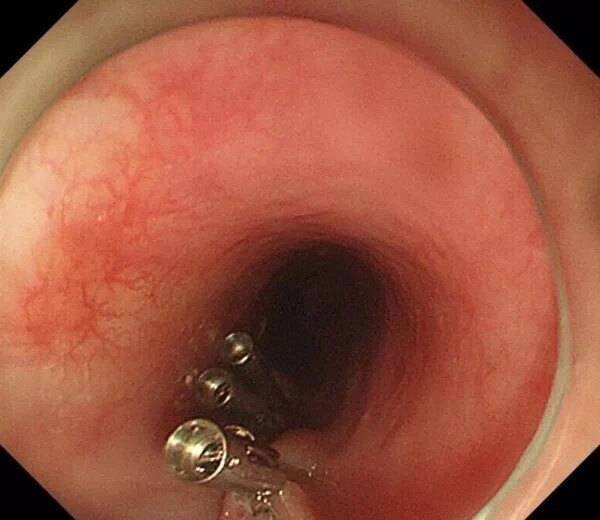

病例分享重度食管静脉曲张上方早癌病变切除手术

图片尺寸664x1088